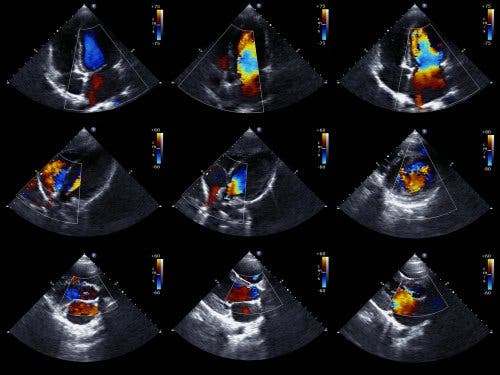

L’ecocardiogramma è l’esame preferenziale per rilevare un versamento pericardico. Viene chiamato anche ecocardiografia o ecografia cardiaca a ultrasuoni. Si tratta di una prova che consente di visualizzare la struttura del cuore e studiarne la capacità di pompaggio del sangue.

L’ecocardiogramma con tecnica Doppler permette anche di stabilire l’esatta velocità dei flussi sanguigni nel cuore. Dal punto di vista tecnico, l’ecocardiogramma bidimensionale e quello M-mode rappresentano la tecnica idonea per diagnosticare, quantificare e monitorare un versamento pericardico.

L’assenza di echi all’interno dell’epicardio e del pericardio laterale consente di diagnosticare un versamento pericardico. Il cardiologo determina le dimensioni del versamento a partire dalla quantità di spazio presente tra i due strati del pericardio.

Esistono due tipi di ecocardiogramma. Quello transtoracico, nel quale si fa uso di un dispositivo che viene collocato sul petto, all’altezza del cuore, e che emette dei suoni. Quello transesofageo, nel quale il dispositivo viene introdotto nell’apparato digerente fino all’esofago. Quest’ultima opzione fornisce dati più dettagliati.